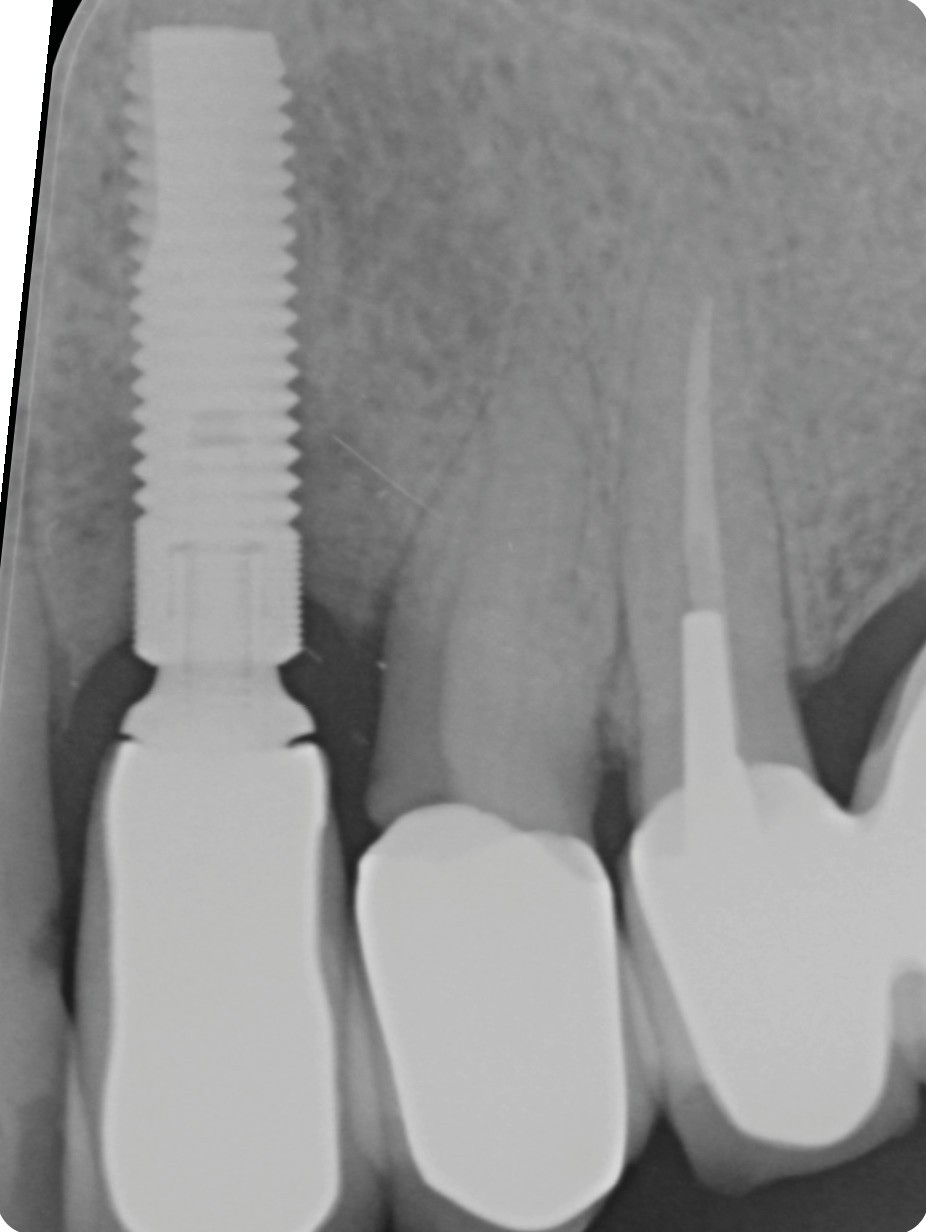

L’implant

- Site 23

- Mis en place il y a 12 ans